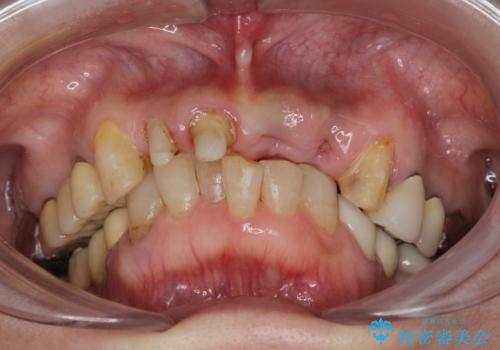

- 歩行中に躓いて転倒し、前歯2本がグラグラになってしまい痛み・審美性の改善を求めて来院されました。

元々の噛み合わせが深く(ディープバイト)、転んで顎を強打したことで上顎前歯2本が根元から折れてしまい抜歯をしなければいけない状況となってしまいました。

今後前歯への負担を減らすためにナイトガードマウスピースを使用していただき歯の保存に努めていきます。